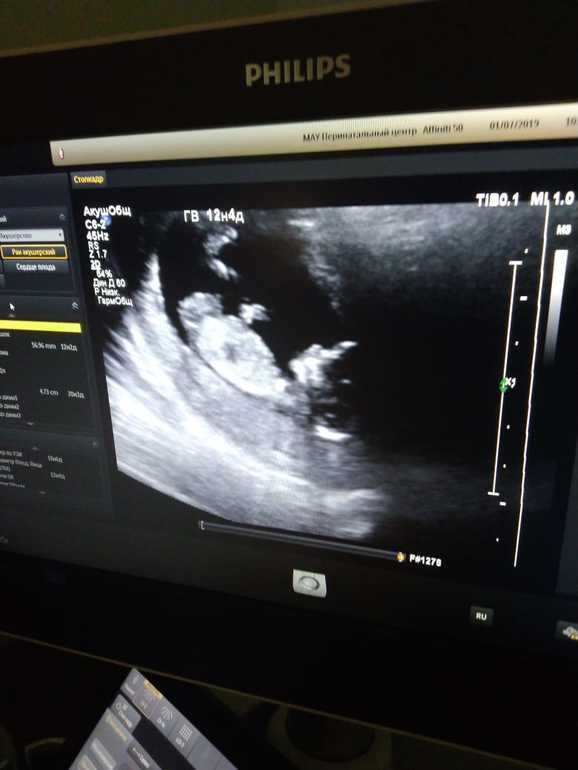

Ура, первый скрининг пройден!

Всё в норме, носовая кость 2,2 мм. Шутим, что будет длинноносый малыш 😃

Проблематично было все показатели замерить, т.к матка у меня загнутая и плохо просматривается. Сфоткала экран на память